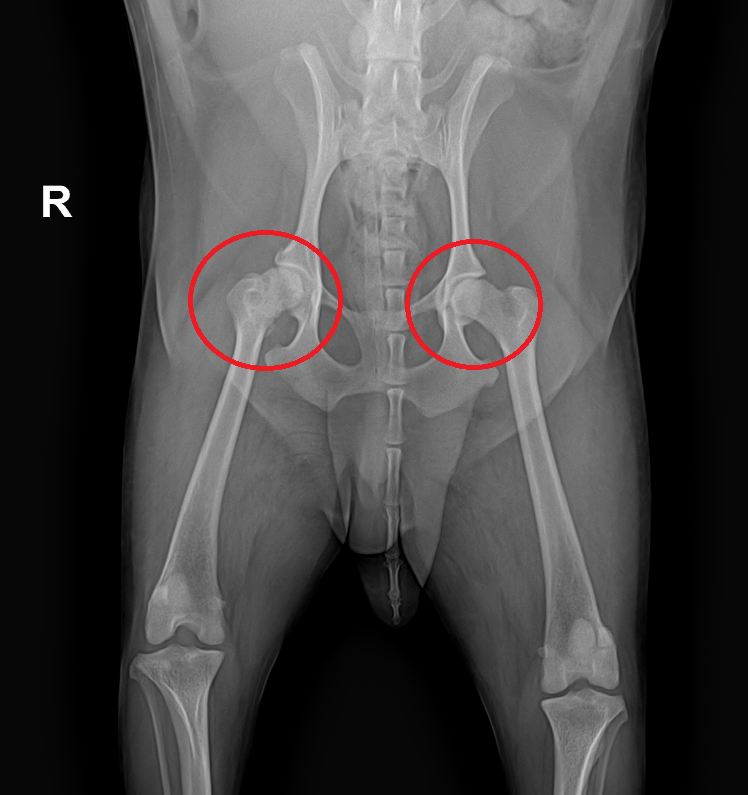

오늘 소개해드릴 아이는 동그라미에 표시된 엉덩이 관절, 즉 고관절 퇴행성 관절염 때문에 아이가 많이 아파했습니다.

학부모님과 상의 후 아이는 양쪽 고관절 수술을 시행하기로 하였습니다.

골두 염증 때문에 사람들이 인공관절을 하는 경우가 많은데 동물들의 경우 여러 가지 이유로 루틴하게 시술하지 않는다고 합니다.위 사진처럼 대퇴골 머리를 제거함으로써 마찰을 줄여 통증을 없애주는 것입니다.

강아지 수술 전후 방사선을 비교하면 이렇게 깔끔하게 수술을 마쳤습니다.앞으로 재활 열심히 하고~ 잘 걸어 다닐 수 있게 해야 해요.이렇게 수술하는 비용은 강아지 몸무게에 따라 가격이 달라집니다.그리고 입원 기간이나 레이저 치료 등 다양한 수술 후의 처치 내용에 따라서도 같은 수술이지만 비용은 달라집니다.굿아빠24시 반려동물건강검진센터 서울특별시 동작구 사당로 289